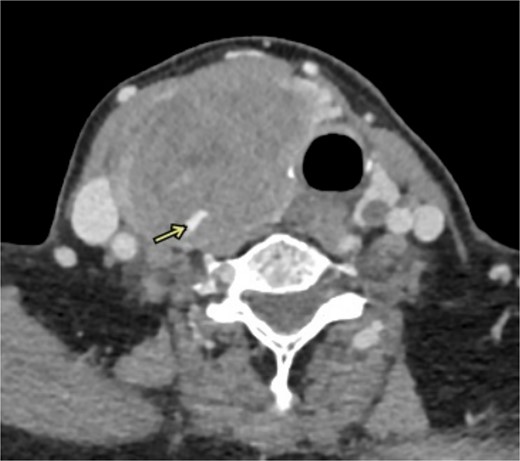

This case study describes a 76-year-old female with a history of type 2 diabetes and hypertension for fifteen years, controlled by her medication. She was swimming when she noted a sudden swelling in her neck. She presented to the emergency department of our hospital with right neck swelling for one-day duration. Physical examination shows a vitally stable patient with a localized neck mass not movable with swallowing and not associated with compressive symptoms. Computed tomography (CT) scan showed significant enlargement of the right thyroid lobe with heterogeneous predominantly hyperdense mass with mass effect on the airway with leftward deviation of the trachea (Fig. 1). Pre-operative CT Angiography showed active extravasation (Fig. 2). Also, there is a suspected right thyroid artery arching over the hematoma. The appearance of the artery raised the possibility of this artery being the cause of the hematoma. Then, a diagnostic angiogram was performed, which showed a dilated, ectatic-looking superior thyroid artery with flow into the hematoma, confirming the source of the hematoma. The patient successfully underwent angioembolization and hematoma evacuation without complications. During the procedure, an unexpectedly large solid component resembling thyroid tissue and a sac surrounding the hematoma were found. The patient was admitted to the Surgical Intensive Care Unit for post-operative monitoring and to prevent potential airway obstruction. The resected specimen was sent for further evaluation by pathology. Gross examination shows large dark brown hemorrhagic mass with thyroid tissue identified measuring 7.5 cm × 0.5 cm. Histopathology examination of the specimen revealed thyroid tissue with extensive hemorrhage and irregular dilated vascular spaces, as well as capillary-like vessels present in thyroid parenchymal tissue. Few thick-walled blood vessels were seen. These vascular channels are lined by bland endothelial cells (Fig. 3A, B). No cellular atypia, mitosis or solid growth pattern was observed. The vascular lining is diffusely positive for CD34, CD31, D2–40, and FLI1 (Fig. 3C, D). Given the above features of histopathology and immunohistochemistry studies, the diagnosis was compatible with primary thyroid hemangioma. Five months post-surgical resection, the patient’s follow-up indicates that she is in good health with no neck swelling, hoarseness of voice, or difficulty tolerating a regular diet. Her wound has healed without any signs of infection.

Coronal imaging of the unenhanced CT shows a large right thyroid lobe heterogeneous mass measuring 9.2 cm × 5.2 cm × 5.5 cm with mass effect on the airway and tracheal displacement to the left.

CT angiography shows active extravasations along the posterior aspect of the right thyroid lobe mass.